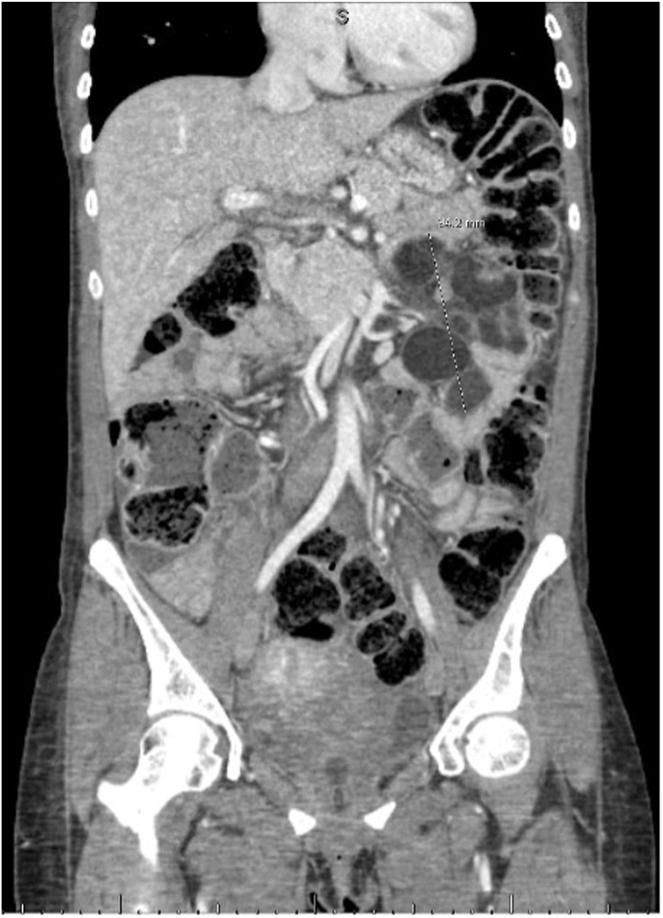

Refractory celiac disease is a rare complex autoimmune-mediated disorder, which has multiple complications, among the best known is enteropathy-associated T-cell lymphoma, other rare complications are central nervous system demyelinating disorder and cavitary mesenteric lymph node syndrome. In our case report, we present a 43-year-old female with a known history of refractory celiac disease who developed a progressive demyelinating disorder of unknown origin and elevated liver enzymes that warranted further investigation. This led to the diagnosis of the cavitary mesenteric lymph node syndrome and celiac disease associated with demyelinating disorder that are both very rare presentations of refractory celiac disease. Treatment options for this case presented a challenge, firstly due to the lack of literature but also to continued complications.

难治性乳糜泻是一种罕见的复杂自身免疫介导性疾病,有多种并发症,其中最广为人知的是肠病相关T细胞淋巴瘤,其他罕见并发症包括中枢神经系统脱髓鞘疾病和空泡性肠系膜淋巴结综合征。在我们的病例报告中,我们介绍了一名43岁女性,她有难治性乳糜泻病史,出现了病因不明的进行性脱髓鞘疾病以及肝酶升高,这需要进一步检查。这导致诊断为空泡性肠系膜淋巴结综合征以及与脱髓鞘疾病相关的乳糜泻,这两种都是难治性乳糜泻非常罕见的表现形式。该病例的治疗选择带来了挑战,首先是由于缺乏文献资料,也由于持续出现的并发症。